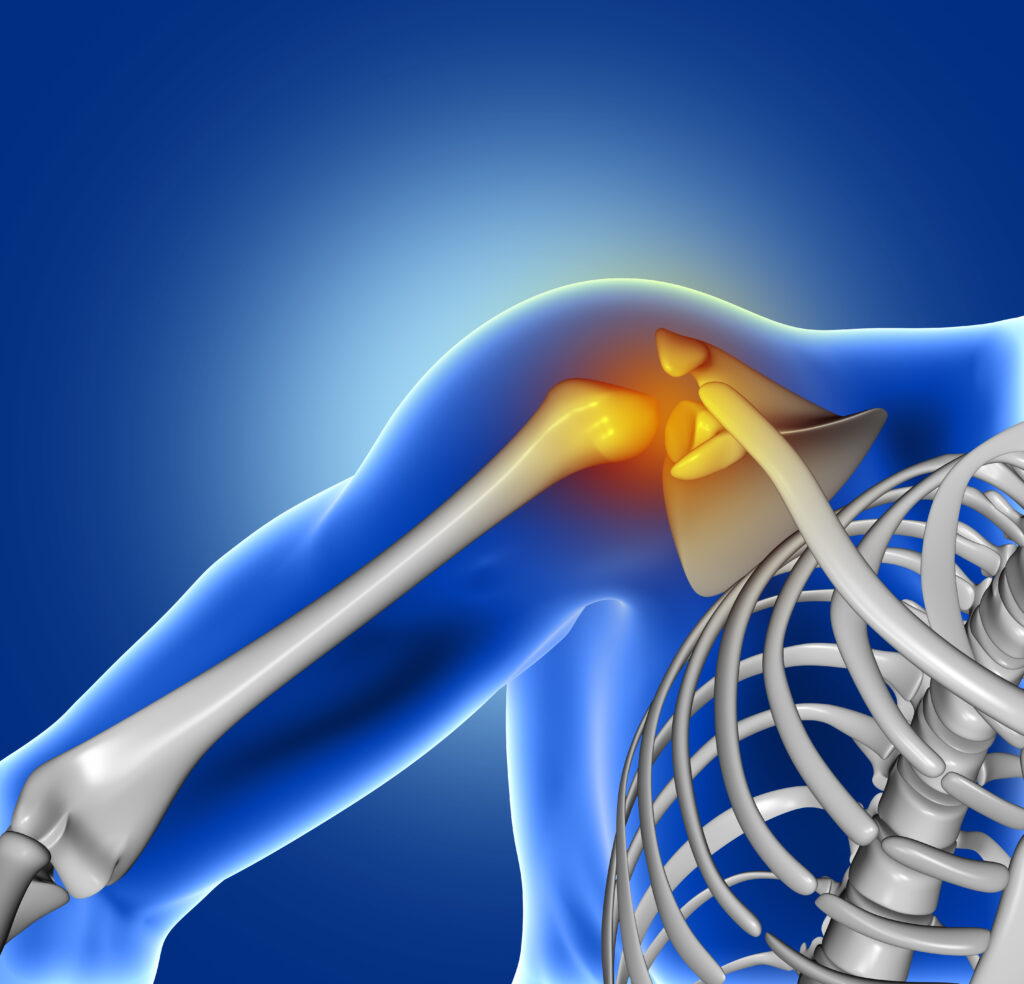

Tratamentul chirurgical al disjuncției acromioclaviculare urmărește restabilirea stabilității anatomice a articulației și reconstrucția ligamentelor rupte.

- Rupturi de ligamente și tendoane